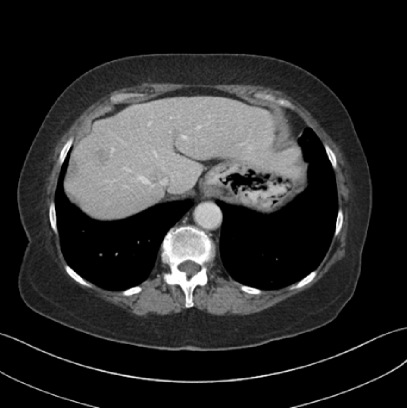

Refer to caption

(a) Clinical Standard Hybrid IR

(b) JENG

Figure 15: An example cross-plane image from the same thoracic dataset as in Fig. 14. (a) A coronal-view image slice of the clinical standard hybrid IR in soft tissue window. (b) JENG at a comparable resolution but with reduced image noise and artifacts.